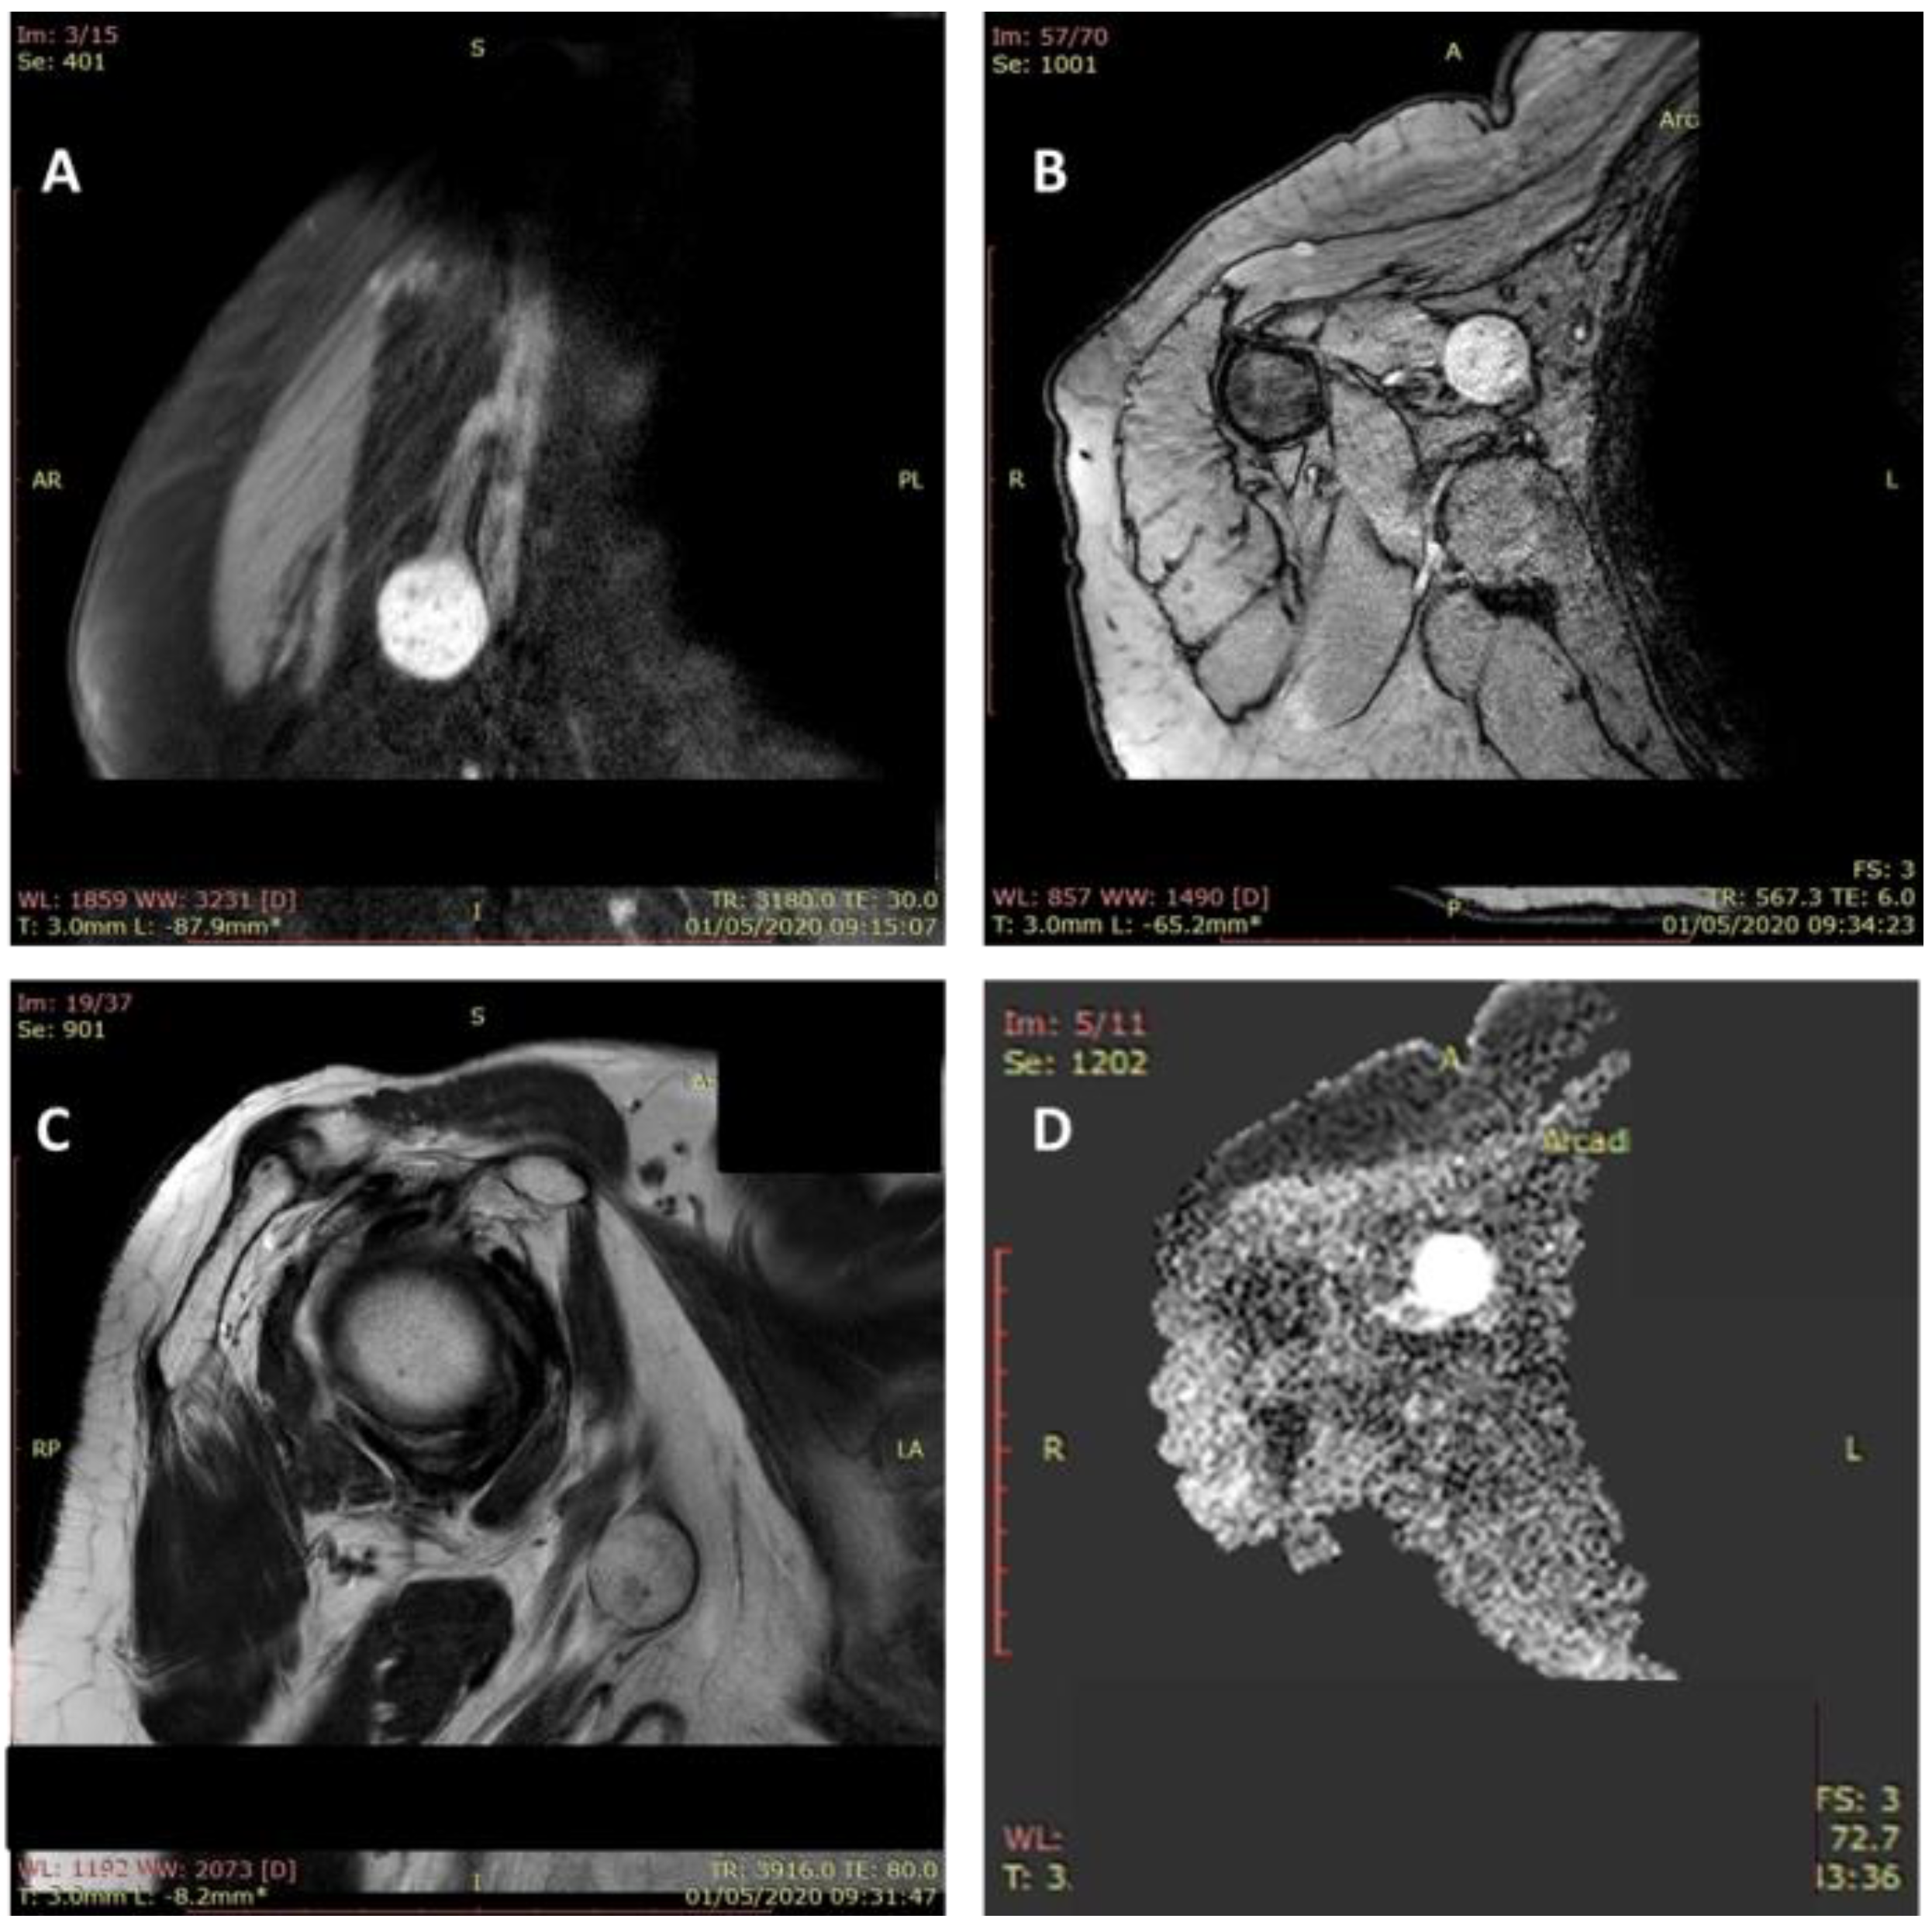

| 5 | 48 | F | + | - | arm | L | ulnar | paresthesia Tinel+ | USG MRI |